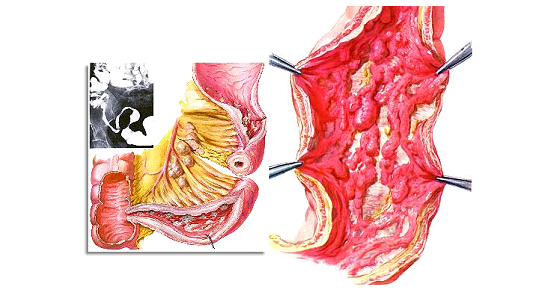

A doença de Crohn é uma inflamação crônica do trato gastrointestinal, que pode afetar qualquer parte do sistema digestivo, desde a boca até o ânus. É uma doença autoimune, provavelmente provocada por um desequilíbrio do sistema imunológico, e a sua causa ainda é desconhecida.